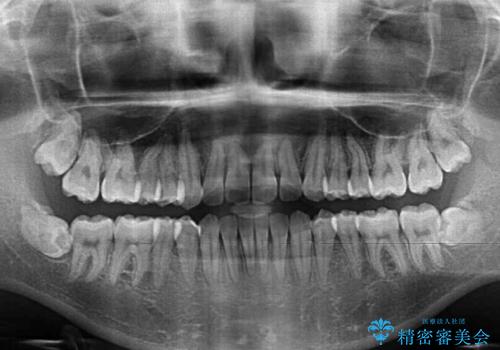

治療開始から4ヶ月ほどで概ね歯列が整い、その後の3ヶ月で細かい部分を仕上げていきました。

短期間で綺麗に仕上がり、患者様には大変満足していただきました。